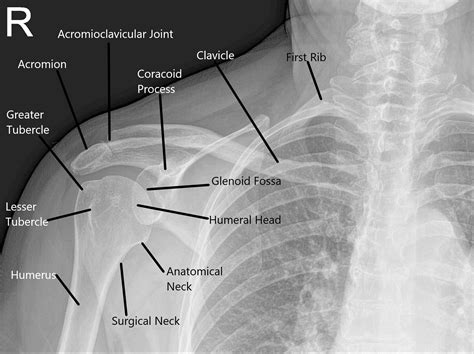

The shoulder joint is a ball-and-socket joint composed of three main bones: the humerus (upper arm bone), the scapula (shoulder blade), and the clavicle (collarbone). The joint is stabilized by a network of muscles, tendons, and ligaments, which allow for a wide range of motion. Understanding the anatomy is essential for interpreting X Ray Shoulder Joint images accurately.

Interpreting X Ray Shoulder Joint results requires a trained eye. Radiologists look for specific signs and abnormalities that indicate various conditions. Some key points to consider include:

• Bone Density: Changes in bone density can indicate conditions like osteoporosis or bone tumors.

• Fractures: Visible breaks or cracks in the bones.

• Joint Space: The space between the bones can indicate the presence of arthritis or other degenerative conditions.

• Soft Tissue: Although X-rays primarily show bones, they can also reveal certain soft tissue abnormalities.

Radiologists use these findings to make a diagnosis and recommend appropriate treatment options.